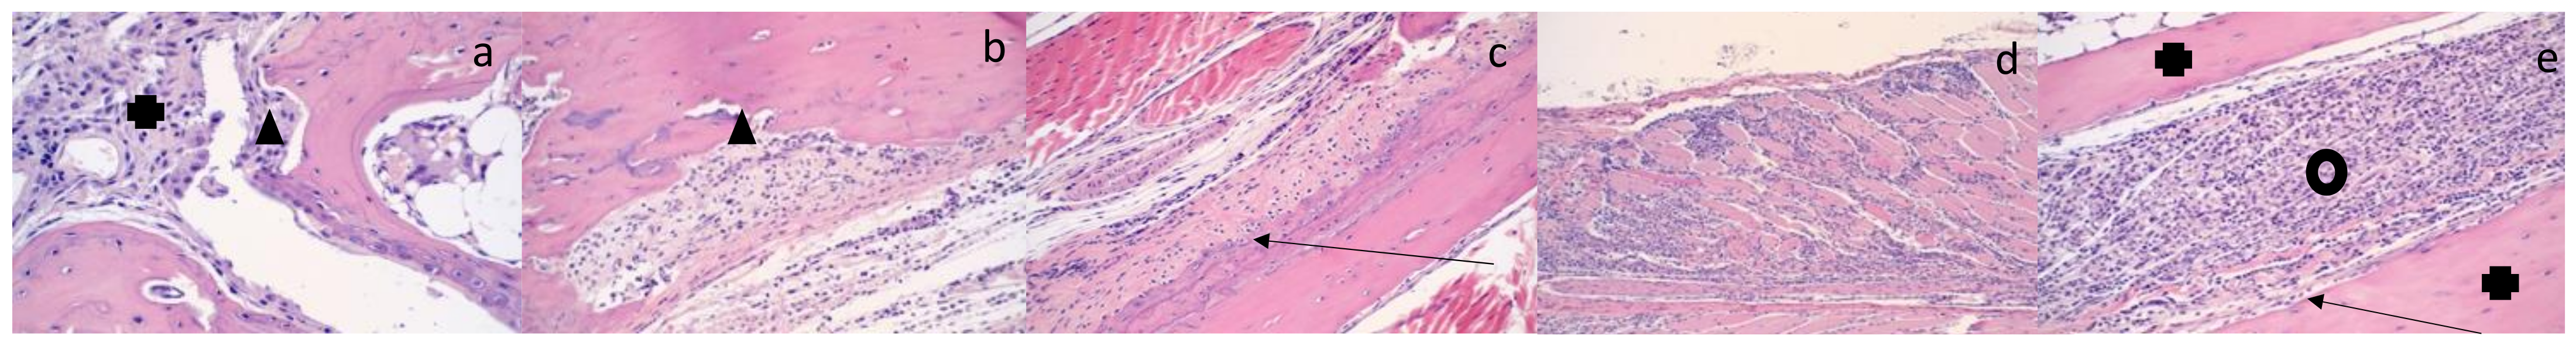

3.4. Histologic Findings: CHIKV SAH2123 Infection Results in Histologic Evidence of Arthritis, Synovitis, Periostitis and Myositis That Persist to 21 DPI